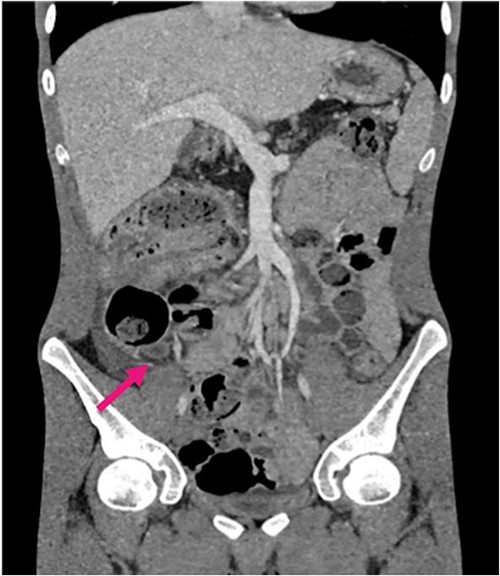

Radiological investigations included a contrast computerized-tomography (CT) of the abdomen/pelvis and suggestive of intussusception of the caecum into the ascending colon, with a thickened appendix. Due to the presence of faecal loading, it was not clear radiologically whether the combined clinical picture was suggestive of distal intestinal syndrome (Figs 1 and 2) due to faecal loading only, or true intussusception of the appendix.

Contrast CT coronal sections depicting the classical ‘bullseye sign’ of intussusception of the caecum into the ascending colon.